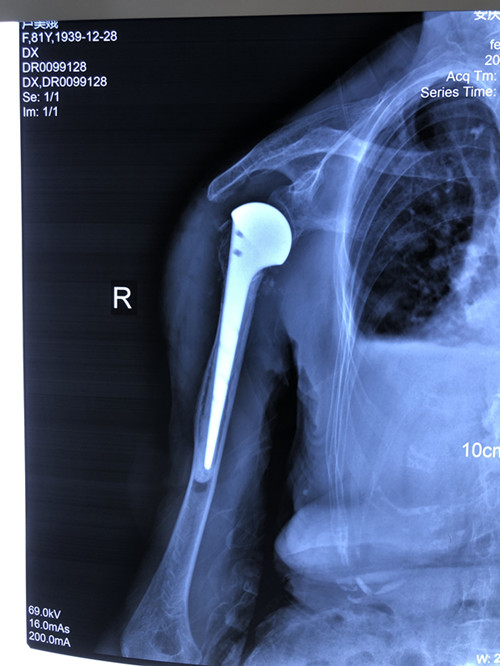

人工肱骨頭置換術(shù)是一個(gè)“精細(xì)活”,技術(shù)要求高、操作難度大,人工假體尺寸的選擇、安放的位置都很有講究。手術(shù)當(dāng)天,張明龍主任帶領(lǐng)團(tuán)隊(duì)僅用時(shí)一個(gè)多小時(shí),就成功將“人工肩關(guān)節(jié)”植入患者體內(nèi)。

術(shù)后,李老太恢復(fù)良好,第3天就開始進(jìn)行輕度被動(dòng)前屈、外展活動(dòng),一周后恢復(fù)擺動(dòng)、康復(fù)功能鍛煉。

攻堅(jiān)克難、不斷創(chuàng)新。此次是石化醫(yī)院骨科團(tuán)隊(duì)首次獨(dú)立完成人工肱骨頭置換術(shù),填補(bǔ)了醫(yī)院該項(xiàng)技術(shù)的空白,也標(biāo)志著科室治療水平又邁上了一個(gè)新的臺(tái)階。